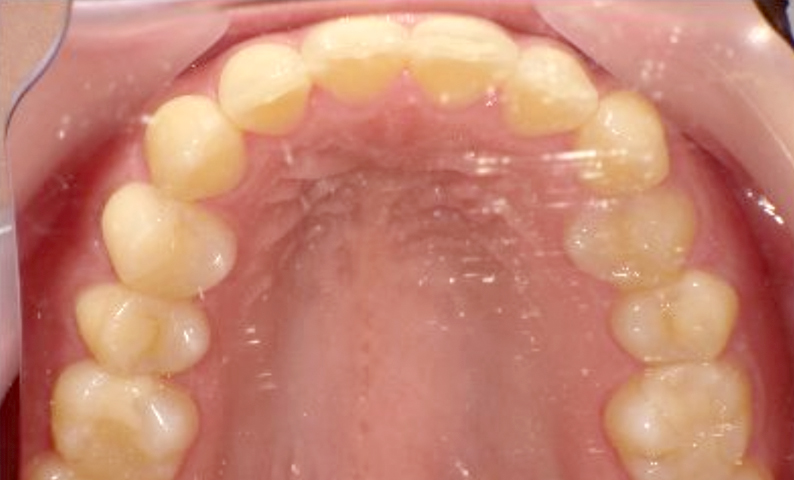

症例_024 上顎だけの部分矯正

治療期間:7ヶ月金額:30万円+税女性前歯のガタガタ上の前歯だけ

| Before | After |